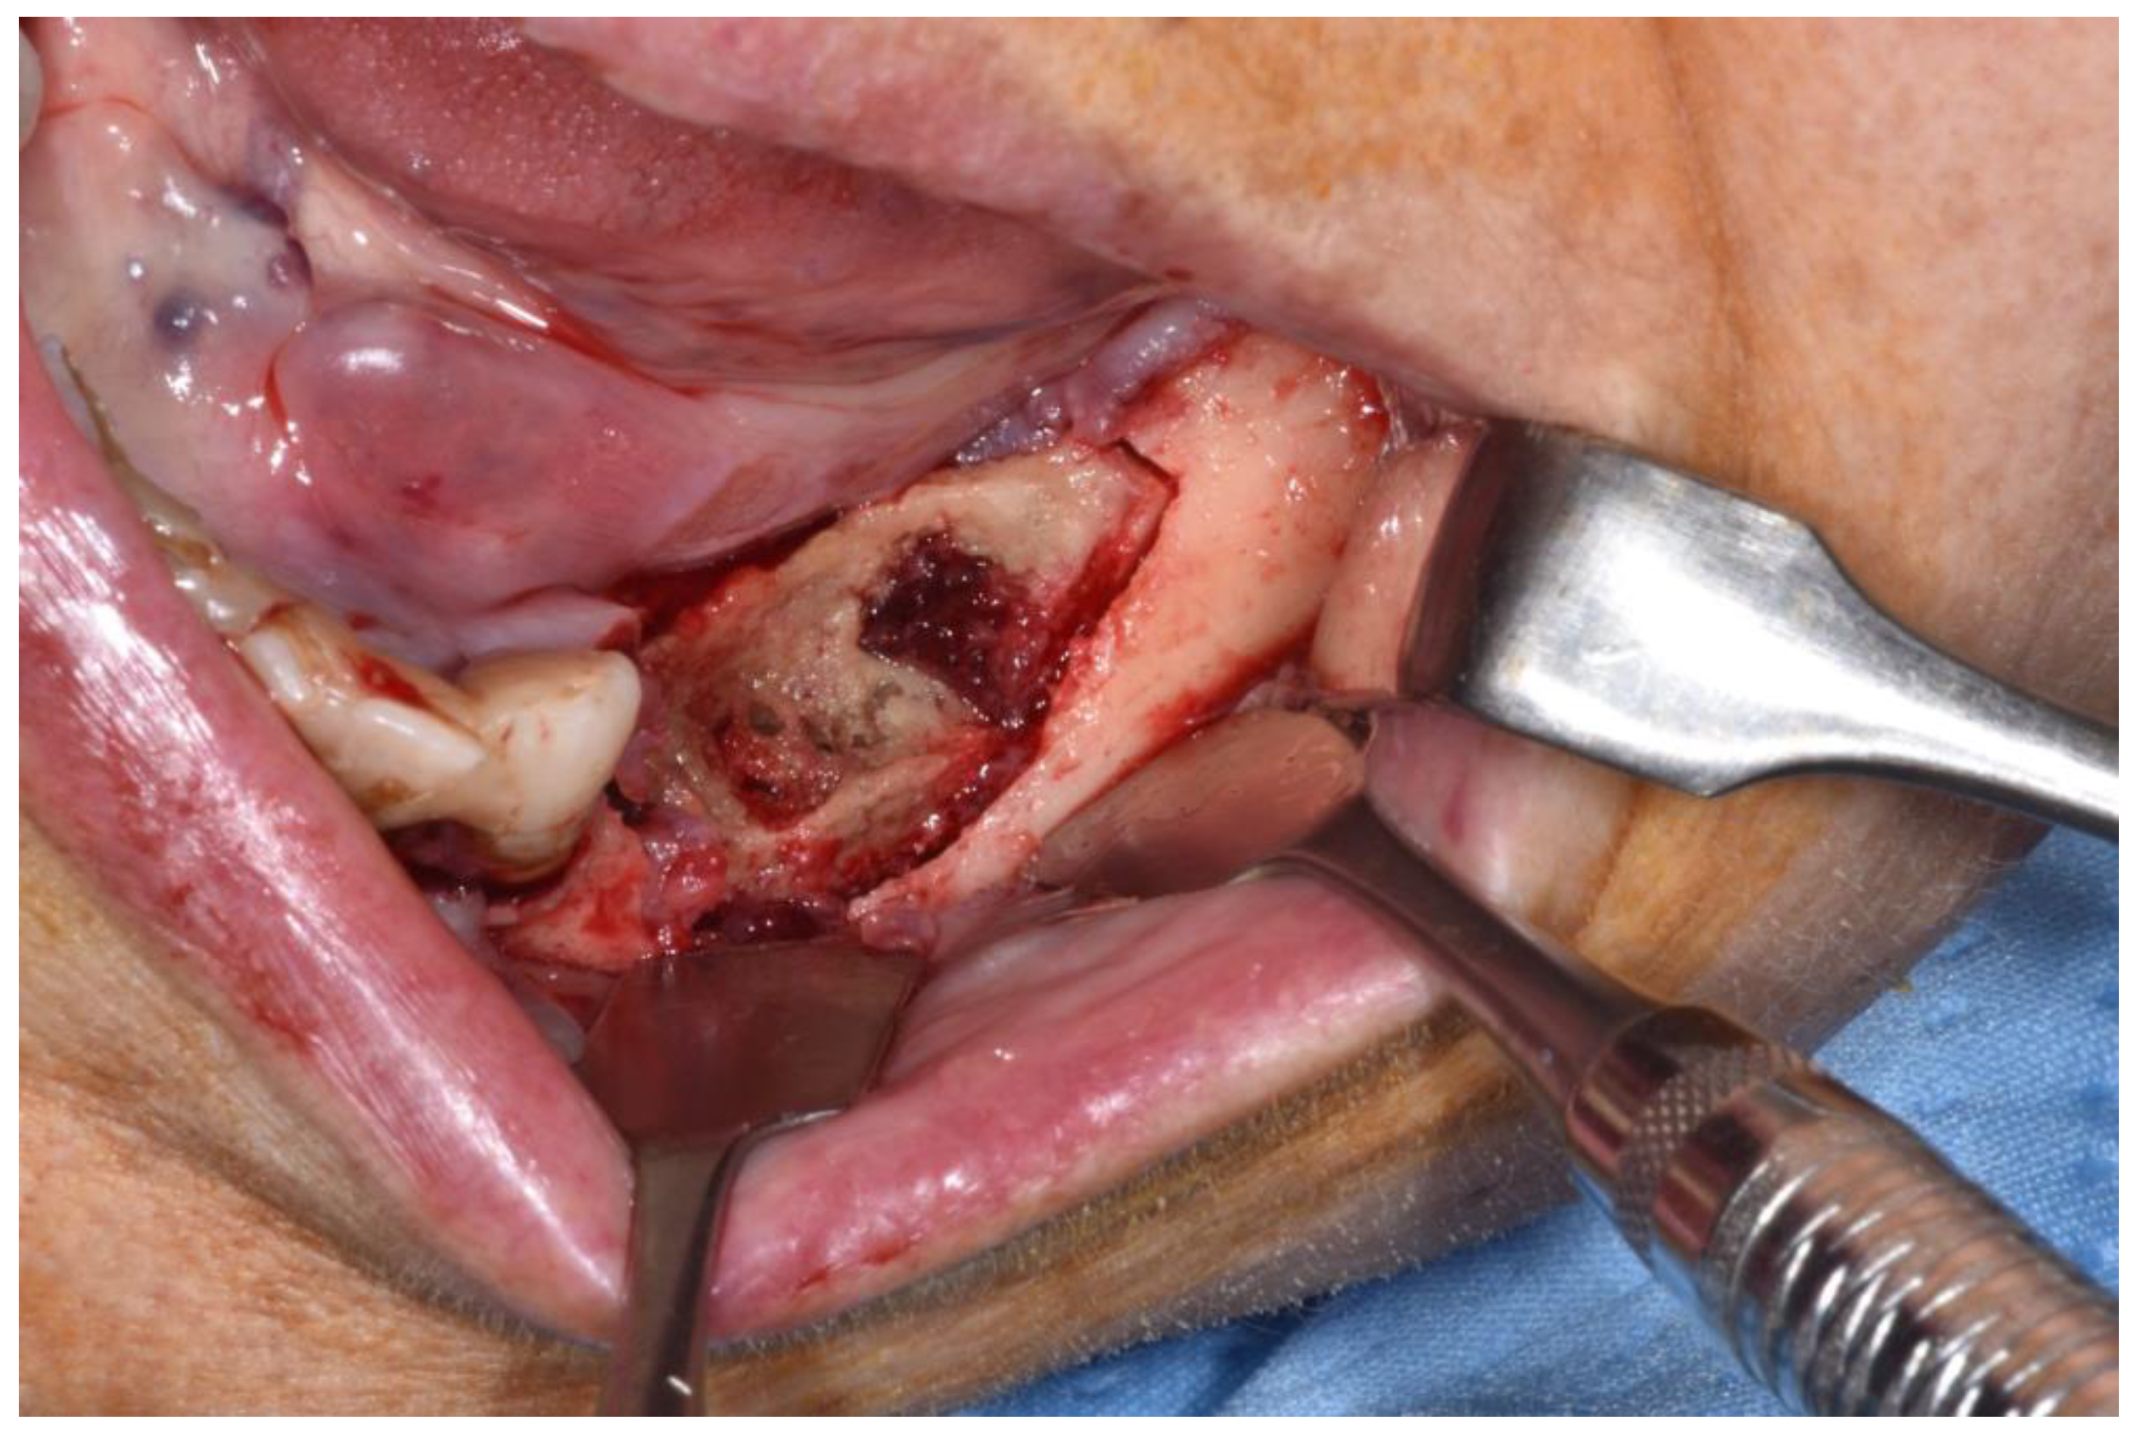

Figure 6.

Revision of the cavity until observing bleeding bone.